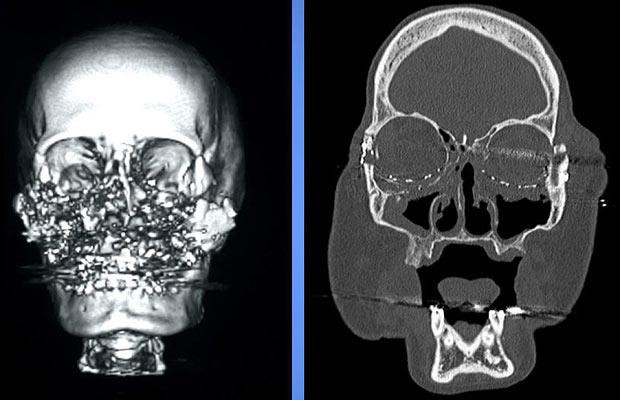

Phát súng oan nghiệt ấy không giết chết Connie nhưng đã thổi bay toàn bộ gương mặt của cô. Mắt, mũi, má, miệng… tất cả đường nét trên gương mặt người vợ đáng thương đã bị phá hủy chỉ còn lại hàng trăm mảnh đạn và xương vỡ lộn xộn. Sau khi bắn vợ, Tom dùng súng tự sát nhưng anh ta cũng may mắn thoát chết.

Năm 2005, Tom bị kết án 7 năm tù giam với tội danh cố ý giết người. Connie đến lúc này vẫn một lòng tha thứ và mong rằng sau khi Tom mãn hạn tù, gia đình họ lại được sum vầy. Những năm tháng sống với “gương mặt quỷ” là thời gian khổ sở, tuyệt vọng nhất trong đời Connie. Cô gần như không mấy ra khỏi nhà bởi với sự biến dạng khuôn mặt có thể khiến cho bất kỳ ai cũng kinh sợ khi nhìn thấy. Cô không còn có khả năng nói chuyện, cười đùa, không thể ngửi hay nếm được mùi vị thức ăn, và để có thể thở bình thường, cổ họng của Connie phải gắn một chiếc ống thông... Sự dằn vặt đau đớn về cả thể xác lẫn tinh thần gặm nhấm Connie mỗi ngày như không bao giờ chấm dứt.

Tháng 12 năm 2008, một phép màu kỳ diệu đã xảy ra. Các bác sĩ đã tìm được một người hiến mặt thích hợp để làm cấy ghép cho Connie. Đây cũng là ca ghép mặt đầu tiên được thực hiện tại Mỹ. Sau cuộc phẫu thuật kéo dài 22 giờ liền, Connie đã được tái sinh với một khuôn mặt hoàn chỉnh. Tiến sĩ Maria Siemionow, Giám đốc nghiên cứu phẫu thuật thẩm mỹ tại Bệnh viện Cleveland, cho biết: “Gương mặt của bệnh nhân vẫn còn rất cứng, cô ấy bị mù mắt phải và bị ảnh hưởng thị lực bên mắt trái, tuy nhiên cô ấy sẽ có thể cười nói, ngửi và nếm thức ăn”.